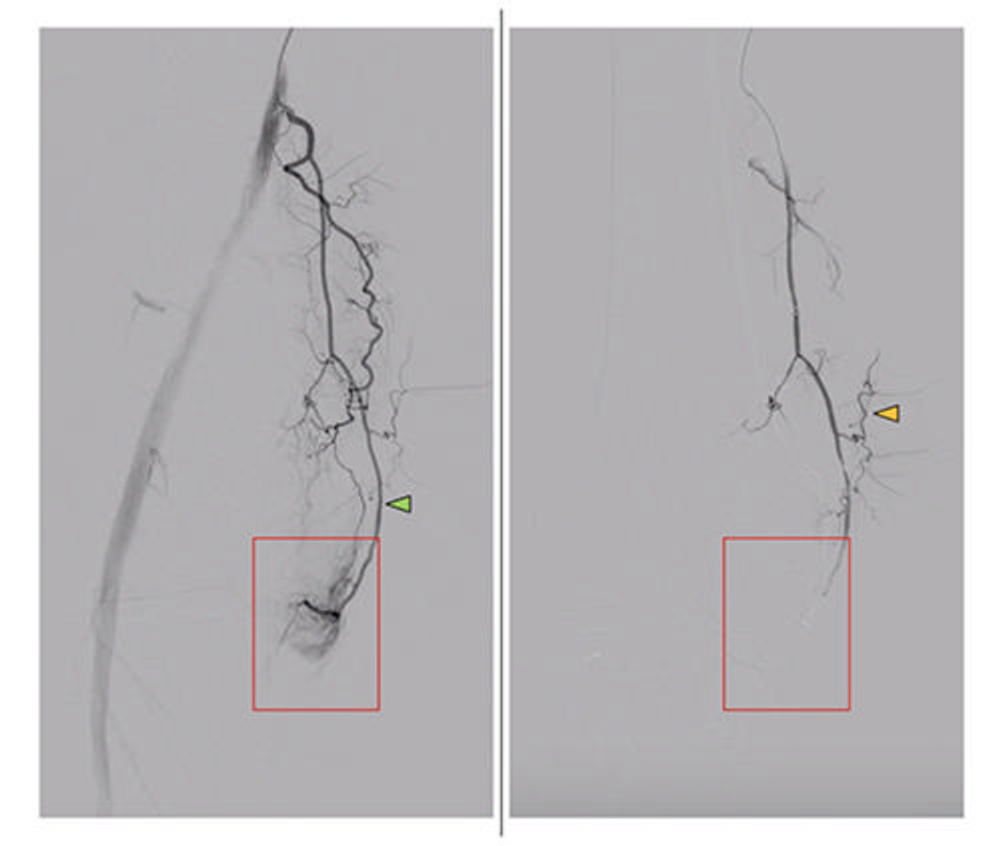

Figure 1. Peri-interventional DSA of the descending genicular artery (DSA), a diagnostic procedure to view the inner surface of blood vessels, (green arrow) in a patient with symptomatic knee osteoarthritis of the right leg. On the left, the pre-interventional image with a clearly visible hyperemic blush (red box). On the right, the post-interventional DSA after embolization with Imepenem-Cilastatin. A completely eliminated blush is observed while preserving skin collaterals (orange arrows).